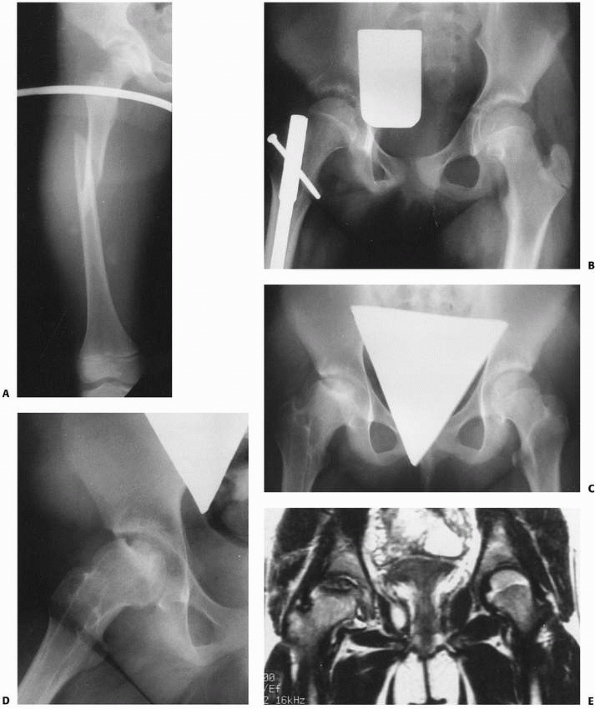

![]() |

FIGURE 22-20 AP (A) and lateral (B)

x-rays a low-energy short oblique fracture through a fibrous cortical defect in the distal femur; this type of fracture is not unusual. The surgeon judged that there was enough distance between the fracture site and the growth plate to allow external fixation. AP (C) and lateral (D) x-rays 3 weeks after external fixation shows early callus and good alignment. The external fixation was removed shortly after this x-ray and the child was placed in a long leg cast, with weight bearing as tolerated. |